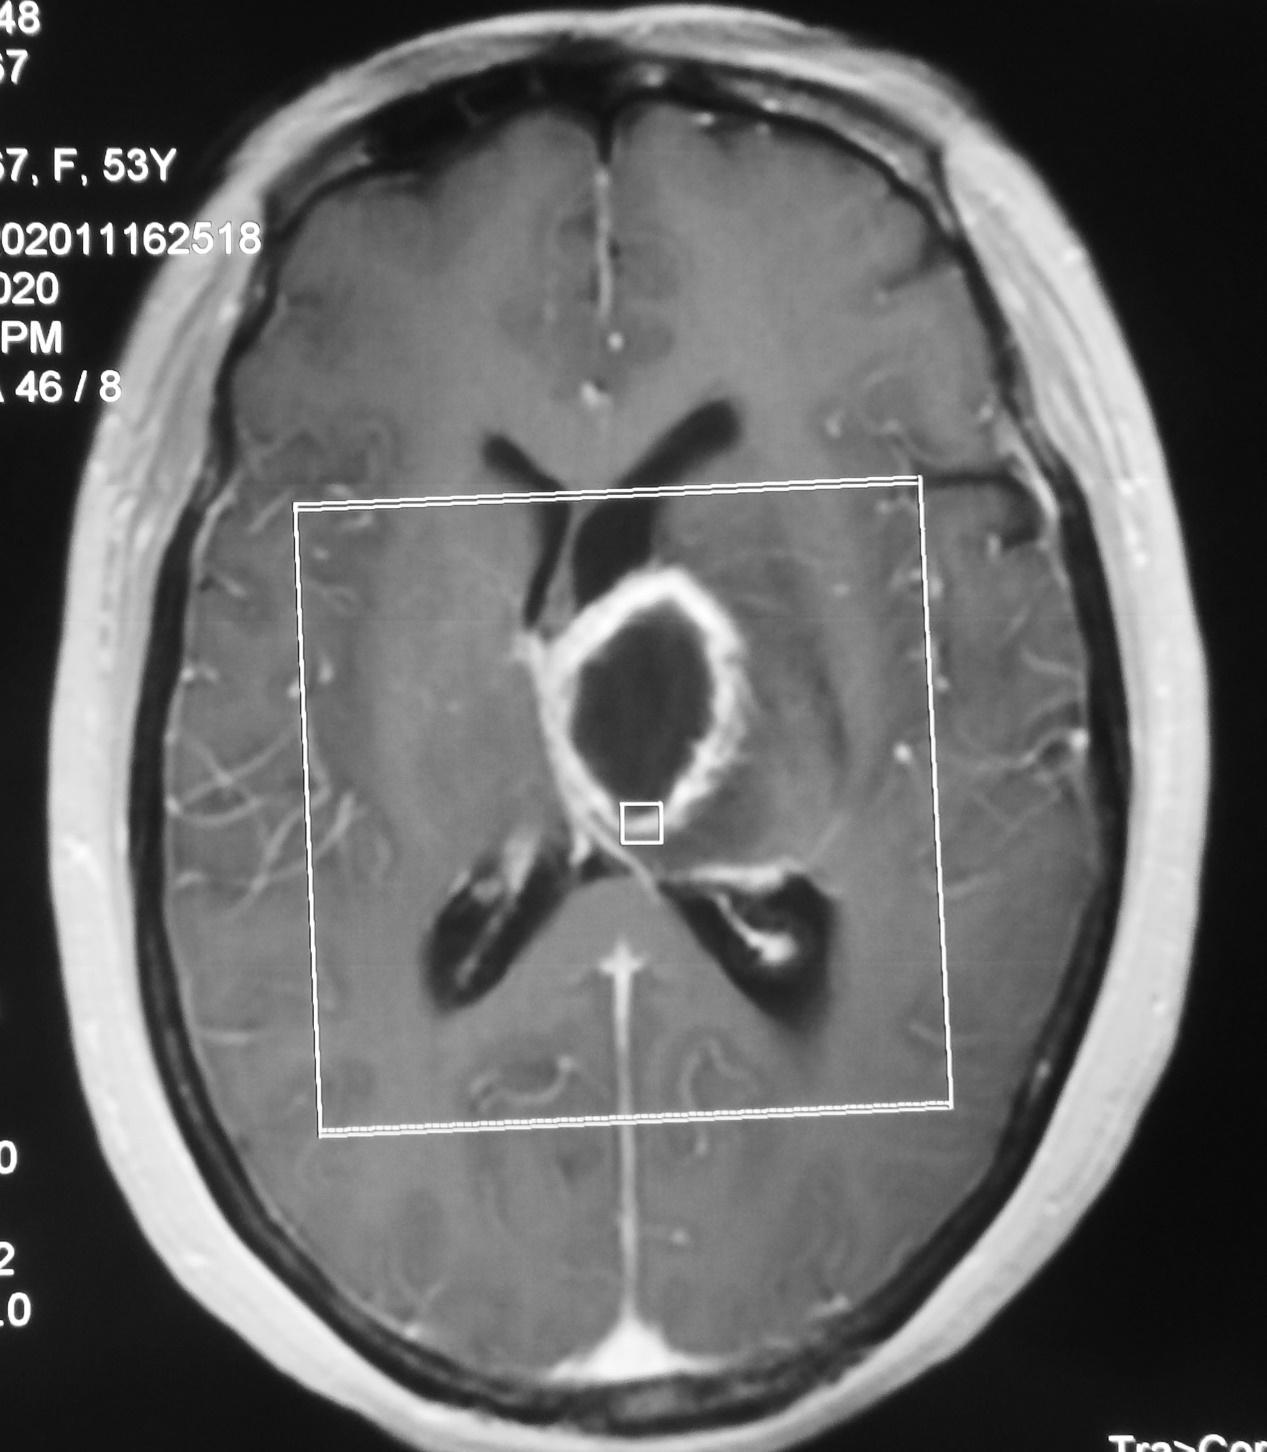

患者病情逐渐加重,出现精神差,饮食差。在当地医生建议下到湖北省武汉市的某三甲医院就诊。于发病后9天即2020年11月17行增强核磁共振检查,发现左丘脑病变明显强化( 图-2 )。当地医生建议手术治疗,但患者担心手术风险较高,于发病后13天即2020年11月21日转到北京某脑科医院。

图-2: 2020年11月17日增强头核磁